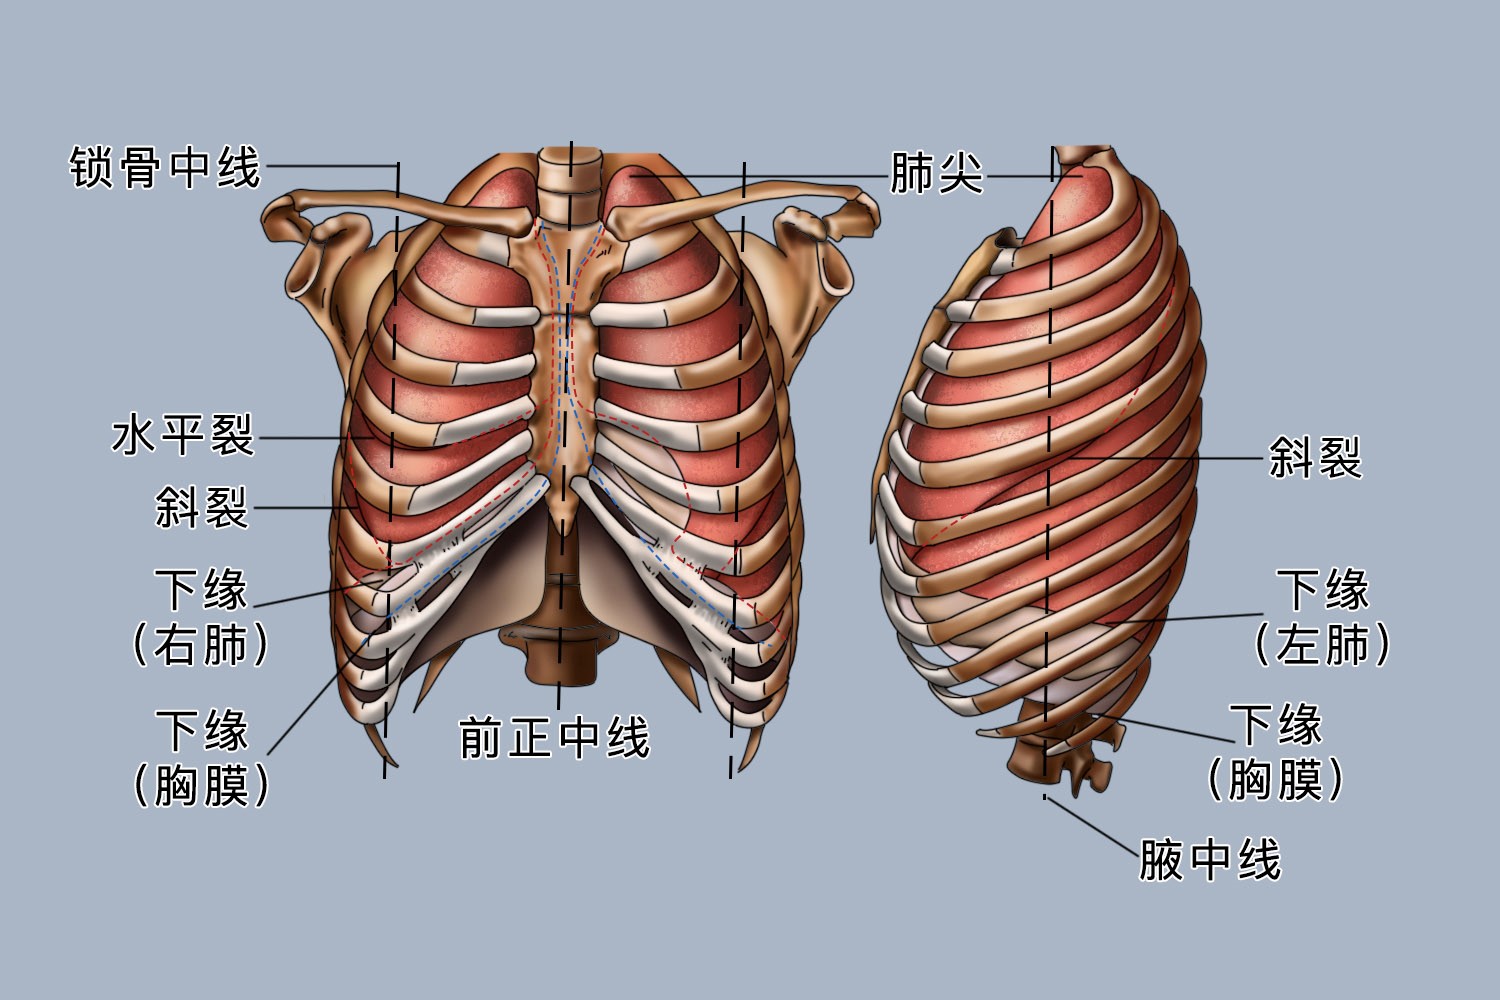

肥的分叶和分段#肺分叶分段 #医学科普 #肺部健康 cr. - 抖音

第四节 肺尖 肺 肺尖 肺底(膈面) 肺的外形 前缘 下缘 肋面 内侧面

肺段分解 - 美篇